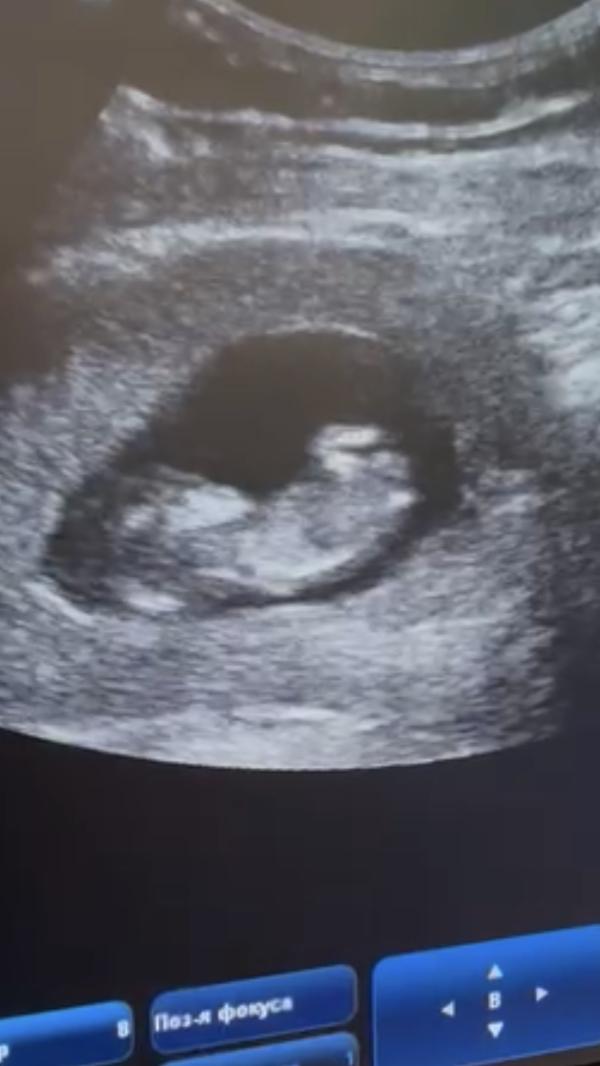

Ты спал, пока тетя водила какой-то штукой по маминому животику, но от моего смеха проснулся 😃 кстати, ты спишь точь-в-точь как твоя мама - ручками к верху 🙃

Мы посчитали твои пальчики - их пять) Ты махал мне ручками, активно толкался ножками, а ещё переворачивался 😃 Это было так забавно смотреть на твои перевороты )

Я очень хотела узнать, кто же ты🧡 но обещала твоему папе устроить все сюрпризом ) Но не сдержалась 😆 И мне предположили, что ты - девочка ❤️